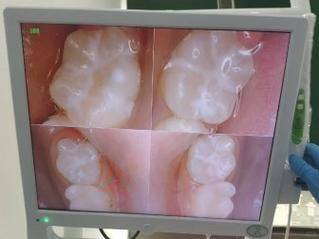

牙齿矫正中 心:采用数字化正畸方案设计,通过口腔扫描获取精细牙列模型,可提前预览矫正成效,开展金属托槽、隐形正畸等多种矫正方式,适配不同患者的矫正需求。

牙齿修复中 心:依托数字化义齿定制技术,制作的修复体贴合度高、美观性强,可开展烤瓷牙冠、全瓷牙冠、活动义齿等修复项目。